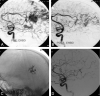

Background and purpose: To report the initial experience by using a new liquid embolic agent (Onyx) for embolization of brain arteriovenous malformations (AVMs).

Methods: Between May 2000 and December 2005, 44 patients with brain AVMs were embolized with Onyx. There were 18 women and 26 men with a mean age of 42.4 years (median 44, range 14-71 years). Clinical presentation included seizures in 26 patients (59%), hemorrhage from the AVM in 13 patients (30%), subarachnoid hemorrhage from a concomitant aneurysm in 3 patients (7%), visual disturbances in 1 patient (2.3%), and in 1 patient (2.3%) the AVM was an incidental finding. Mean estimated size of the AVM was 3.9 cm (median 4, range 2-7 cm).

Results: In 44 patients, 52 embolization procedures were performed with 138 feeding pedicles embolized, ranging from 1 to 7 per patient. Average estimated size reduction was 75% (median 80%, range 40%-100%). Total obliteration was achieved in 7 AVMs (16%), and partial embolization was followed by surgery in 10 patients and by radiosurgery in 20 patients. Complications occurred in 6 patients, leading to death in 1 patient (mortality 2.3%) and to permanent disability in 2 patients (morbidity 4.6%).

Conclusion: Onyx is feasible and safe in the embolization of brain AVMs. Complete obliteration can be achieved in small AVMs. Large AVMs can be adequately reduced in size for additional surgical or radiosurgical treatment.